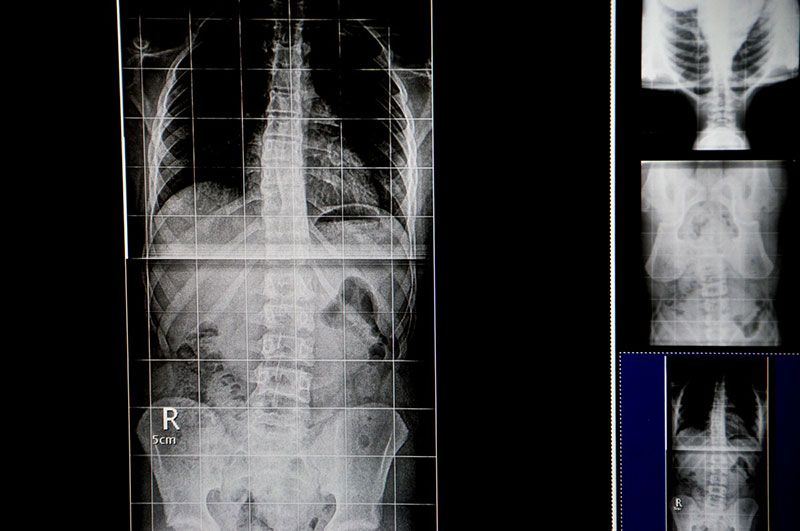

Ψηφιακός Έλεγχος Σπονδυλικής Στήλης και Ανισοσκελίας (Full Spine & Full Leg)

Στο κέντρο μας είναι το μοναδικό στην περιοχή των Δωδεκανήσων, που προσφέρει τη δυνατότητα απεικόνισης ολόκληρης της σπονδυλικής στήλης σε μια ακτινογραφία (full-spine-length). Έτσι με μια ακτινογραφία και ελάχιστη ακτινοβολία μπορούμε να έχουμε εικόνα από ολόκληρη τη σπονδυλική στήλη και τη λεκάνη.

Το συγκεκριμένο διαγνωστικό εργαλείο είναι ιδιαίτερα σημαντικό για προληπτικό έλεγχο (κυρίως των εφήβων) σε θέματα:

• Σκολίωσης

• Κύφωσης

• Λόρδωσης

• Ανισοσκελίας